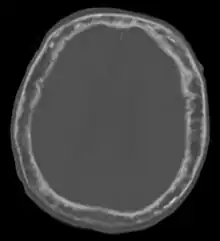

| "This 92 year-old male patient presented for assessment of sudden inability to move half his body. An incidental finding was marked thickening of the calvarium. The diploic space is widened and there are ill-defined sclerotic and lucent areas throughout. The cortex is thickened and irregular. The findings probably correspond to the 'cotton wool spots' seen on plain films in the later stages of Paget’s disease." | |